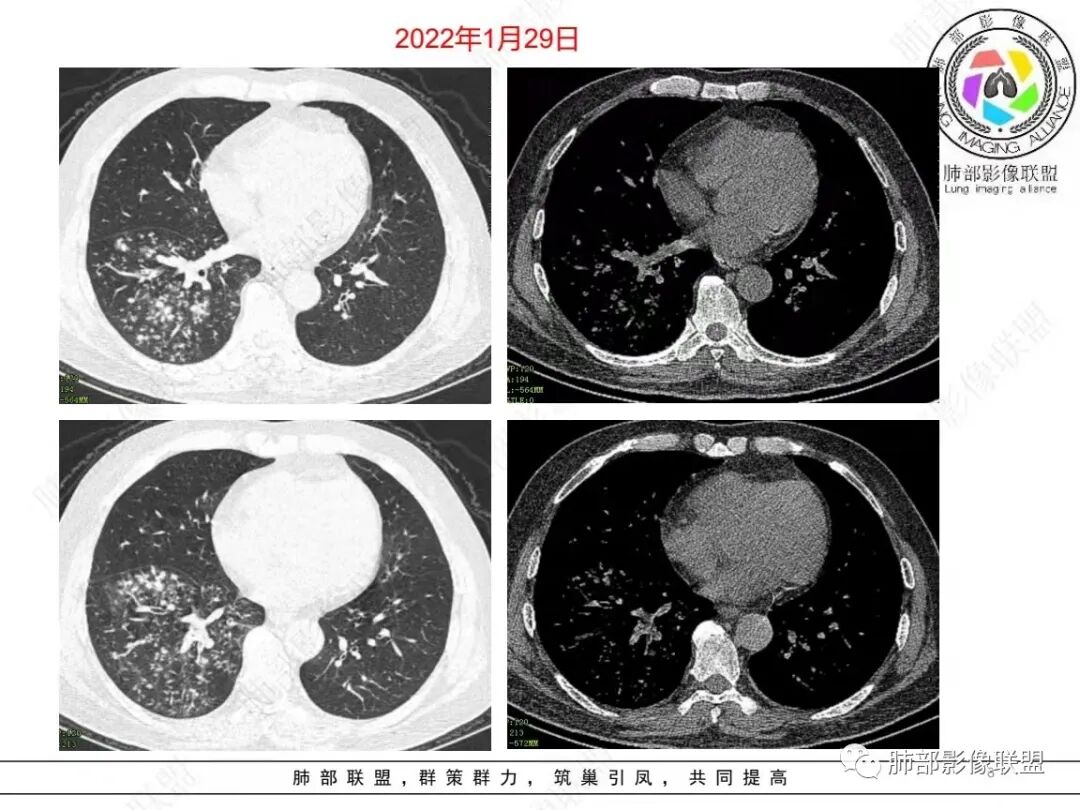

老年男性,糖尿病人,右下肺弥漫性小叶核心结节,治疗10天后明显吸收,血象高,中性粒细胞计数高,pct略高,首先考虑金葡菌感染,鉴别G-肠杆菌

右肺下叶多发腺泡结节影,边缘部分模糊,伴树芽征,支气管壁增厚,10天复查腺泡结节有吸收变淡,病变内出现多发囊状影,考虑感染性病变,金葡?真菌?

右肺下叶多发腺泡结节影及树芽征,抗炎治疗后吸收好转,白细胞及中性明显增高,有糖尿病病史,首先考虑气道来源感染性病变,金葡菌?吸入?

中年男性,咳嗽咳黄脓痰一周,有糖尿病,肾病病史,长期使用激素血象白细胞自然会升高,但CRP明显升高。降钙素原不高,肺泡灌洗液阴性。右下肺沿支气管分布腺泡结节影,少于树芽征,小实变影,支气管壁轻度增厚,考虑感染性疾病,从病灶形态来看气道来源,复查病灶有小空洞形成,病灶明显吸收。考虑气道金葡菌肺炎,鉴别奴卡菌

中老年 男性 白细胞高,基础病多, 右肺下叶多发小结节 小斑片影,边缘模糊,伴树芽征,支气管壁略增厚,短期治疗后复查病灶有所吸收,可见小囊状透光区形成,考虑气道来源化脓性感染,金葡 可能

中老年男性,糖尿病史,免疫抑制,白细胞及C反应蛋白明显升高,右肺下叶多发腺泡结节、树芽,边缘模糊,支气管管壁增厚,治疗10日复查吸收好转,可见小空洞,考虑金葡,鉴别曲霉

57岁男性,糖尿病、肾病基础。白细胞升高、以中性升高为主,黄浓痰提示细菌感染、球菌可能大。结核几次相关检查都阴性,可能性不大。几次血培养无细菌生长,结合影像,病灶不是血播而是气道播散。影像:沿气道播散,树芽明显,(树芽有没有特征?部分枝细芽大?),部分支气管弥漫增厚,治疗10后复查,临床没有怀疑真菌类,结核阴性,所以抗结核抗真菌的可能小,只能是抗炎治疗10天后复查,树芽缩小、部分消散,支气管壁变薄,提示抗菌有效,但部分出现了气囊空洞。细菌、空洞、黄浓痰,加起来,首先考虑金葡菌支气管播撒应该顺理成章。

病变区支气管壁弥漫增厚,远端树芽征,周围GGO——渗出